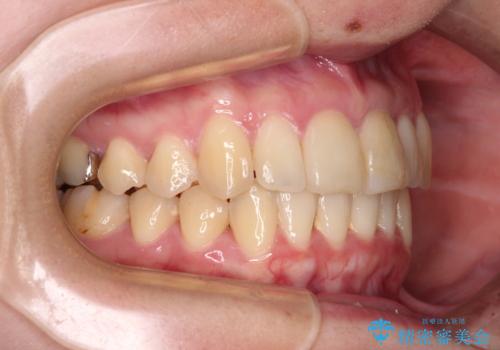

上下前歯のデコボコをきれいに インビザラインによる矯正治療

- 前歯の著しい叢生と前突感を気にして来院された患者様です。

叢生が強いため、事前に前歯をワイヤー矯正で速やかに叢生を解消し、その後はインビザラインにて矯正治療を行うこととしました。

ワイヤー矯正を併用したことで前歯の叢生を速やかに解消することができました。

一方口元の突出感を改善するために時間がかかり、2年超を要しましたが、満足のいく仕上がりとなりました。